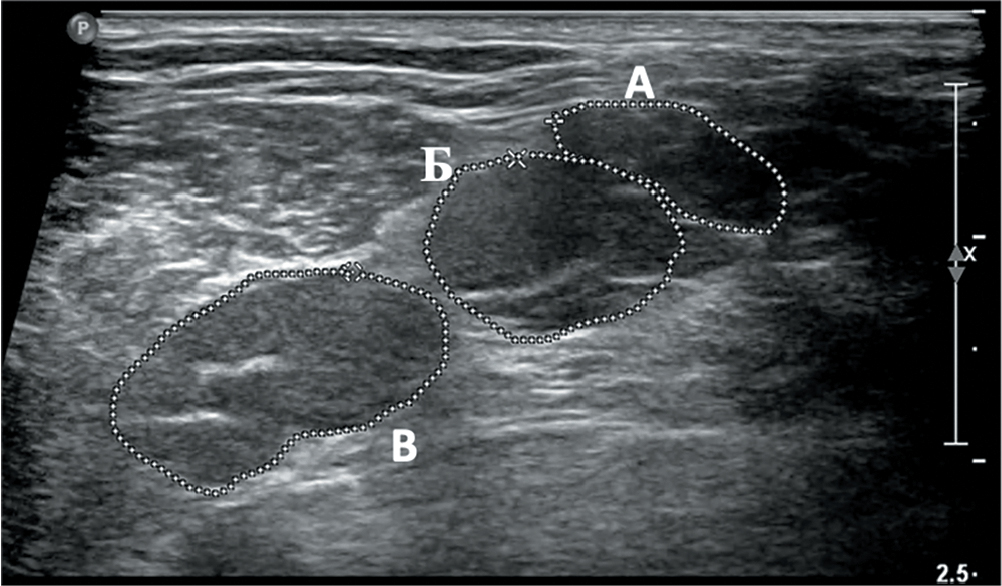

Увеличение диаметра спинномозговых нервов и ППС стволов ПС при УЗИ данных структур выявлено у 26 (87%) пациентов с ММН и у 32 (94%) пациентов с мХВДП. При этом исключительно односторонние изменения визуализировались у 6 (23%) из 26 пациентов с ММН и 3 (9%) из 32 пациентов с мХВДП (рис. 2).

Рис. 2. Сонографическое исследование стволов ПС у пациента с мХВДП (катамнез 8 лет, исследование выполнено до начала патогенетической терапии). При поперечном сканировании в межлестничном промежутке визуализируются три первичных ствола с увеличением ППС верхнего до 33,6 мм2 ( А), среднего до 68,9 мм2 ( В) и нижнего до 94,8 мм2 (С) (норма < 8 мм2).

Fig. 2. USG of BP trunks in a patient with MADSAM (8-year follow-up history, pre-therapy assessment). In the cross section, three primary trunks are seen in the scalene part, with enlarged upper (≤ 33.6 mm2; А), middle (≤ 68.9 mm2; В),

and lower (≤ 94.8 mm2; С) primary trunks (reference < 8 mm2).